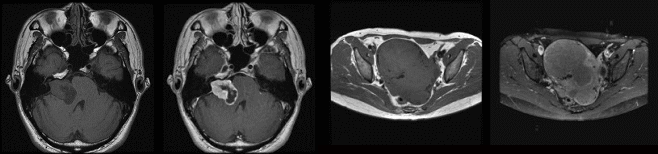

頭部・頸部・乳房・胸部・腹部・骨盤・脊椎・脊髄・四肢・関節・MRA・MRCPなど。